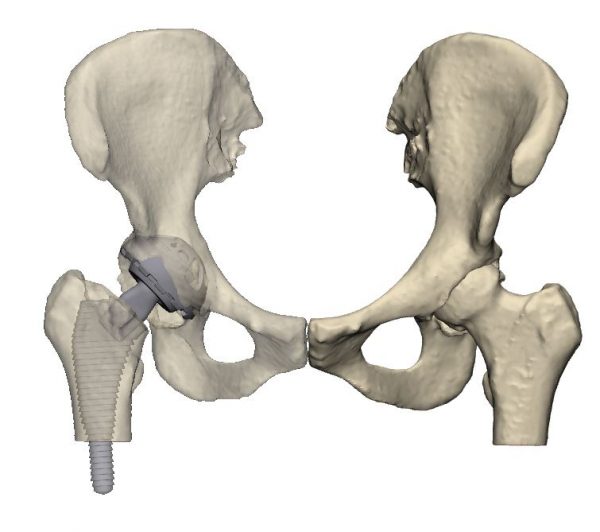

L’artroplàstia és una intervenció quirúrgica en la qual s’extreuen parts d’una articulació danyada i se substitueixen per una pròtesi de metall, plàstic o ceràmica d’una articulació sana. El 2019 es van realitzar més de tres milions de substitucions articulars a Europa i, a mesura que la població envelleix, es preveu que el nombre d’intervencions augmenti cada any. Tanmateix, la substitució articular és una operació complexa i un dels factors determinants més importants per a l’èxit és l’ajust de l’implant al cos i la seva adequació a característiques específiques de cada pacient com el sexe, l’alçada, el pes i l’edat.

Aquesta solució ha consistit en un conjunt d’eines i programes informàtics per al disseny, planificació i impressió 3D no aplicades fins ara a l’assistència sanitària, que funcionen de manera coordinada per agilitzar i millorar la qualitat dels processos quirúrgics. En concret, la solució incorpora: impressores 3D que amplien la capacitat productiva de l’I3PT i redueixen els temps en la fase de disseny; eines d’escaneig 3D per al mesurament de precisió preoperatòria de forma no invasiva que permeten l’avaluació de tot el cos per a optimitzar la biomecànica personalitzada, substituint així en algunes ocasions el TAC; i programari per a monitorar i realitzar un seguiment de principi a fi dels processos de fabricació i quirúrgics, garantint la qualitat necessària per a produir una pròtesi biomecànica personalitzada.

Planificació quirúrgica virtual per artroplàstia de maluc (foto superior) i espatlla (foto inferior)